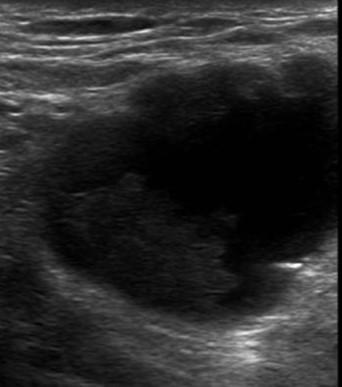

Ung thư vú

» Thông tin: Nữ giới – 57 tuổi.

» Lâm sàng: Khối tuyến vú.